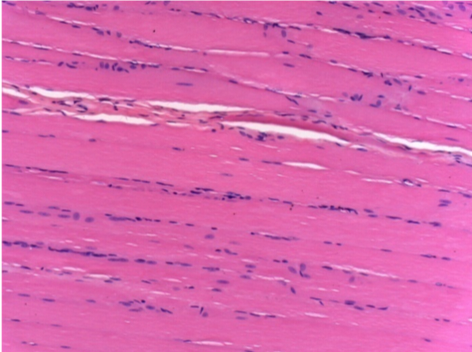

3 months (D90)after Endopeel Injection 0.1ml in the right pretibial muscle.

7 months (D210)after Endopeel IM Injection 0.1ml in the right pretibial muscle.

Complete Restitutio ad integrum after 7 months